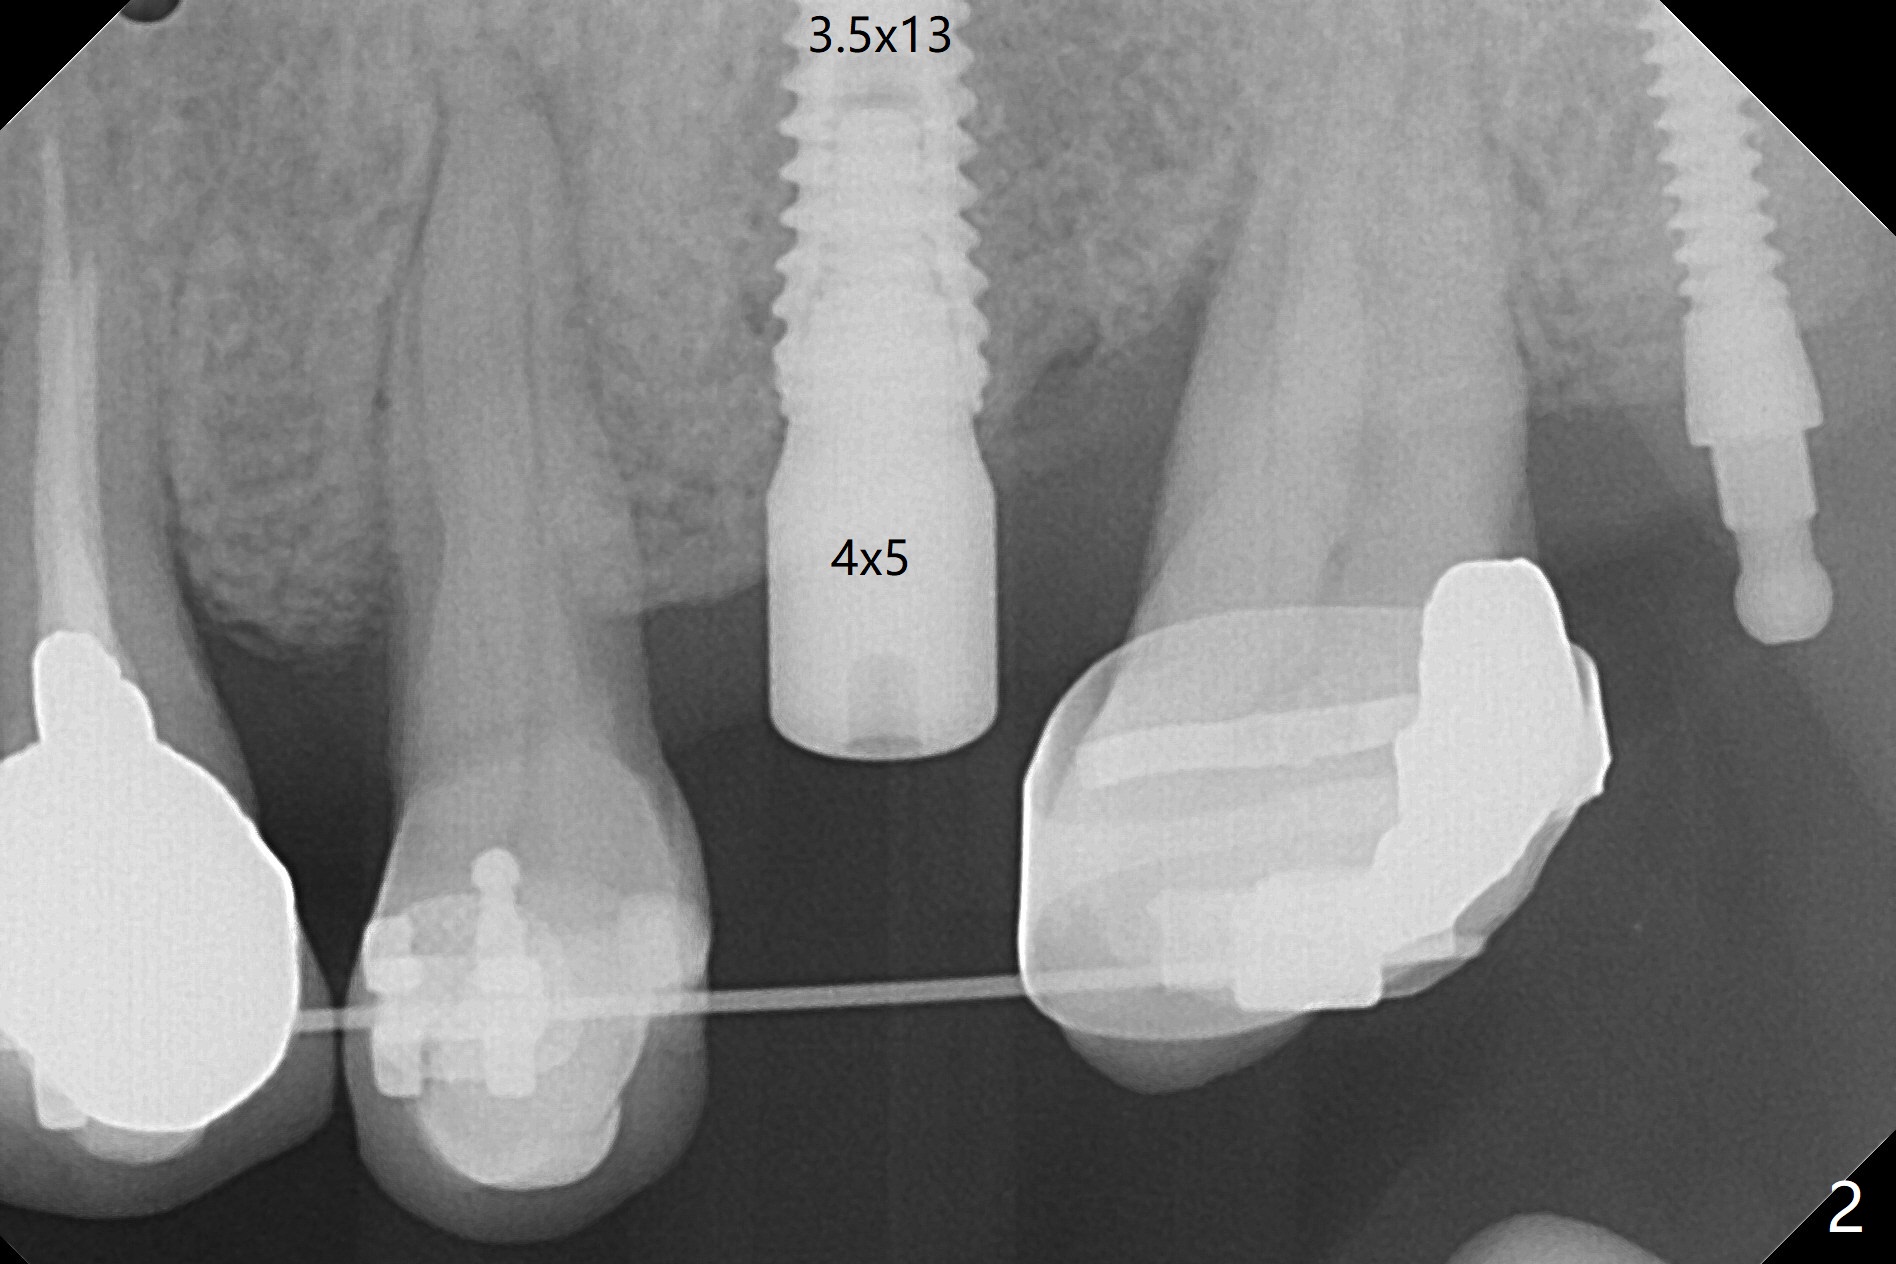

Eight-month limited ortho including use of a 1-piece implant (Fig.3 P (ball type)) as a distal anchor increases the mesiodistal space of #14 from <4 mm to 6 mm (near premolar width).  Guided surgery is not indicated because of presence of brackets and band and the narrow space.  Also due to the latter, incision is difficult to make.  In stead a 3.5 mm tissue punch is applied.  After 2.2 mm drill, a parallel pin is placed; it appears that the initial osteotomy is palatal (Fig.1).  Lindamann bur is adopted to move the osteotomy buccal.  The last drill (3 mm for 3.5 mm implant) has no resistance when it enters the buccalized osteotomy.  A longer implant than designed is placed (3.5x13 mm, Fig.2,3, close to the sinus floor (dashed yellow line) with 50 Ncm.  When the implant osteointegrates, it will be used a mesial anchor to distalize the 2nd molar.